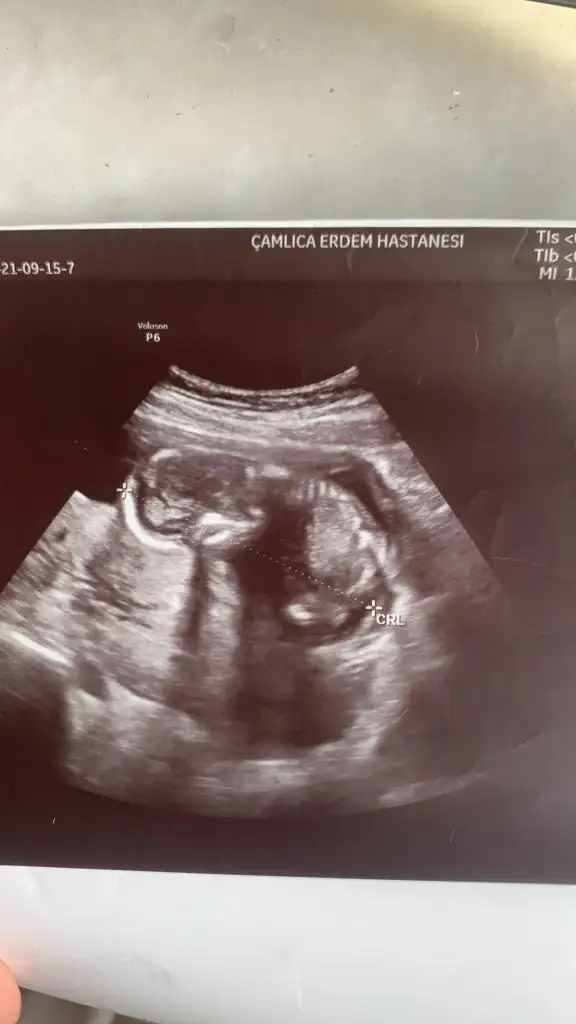

Rica etsem benim 11+6 ve 12+3 haftalık usg görüntülerine de tahminde bulunabilirmisinizUygun değil başka USG varsa paylaşın 11 12 13 haftalar olmalı

Emin olmadım erkek gibi sanki başka USG paylaşınRica etsem benim 11+6 ve 12+3 haftalık usg görüntülerine de tahminde bulunabilirmisiniz